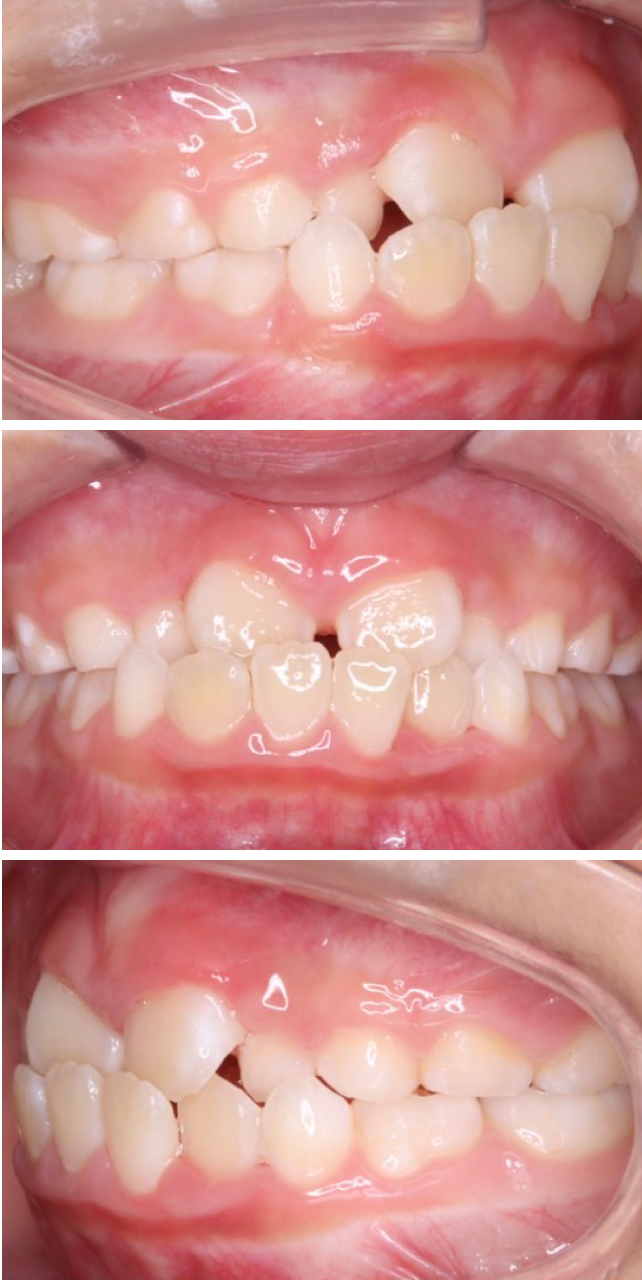

当院の症例

CASE